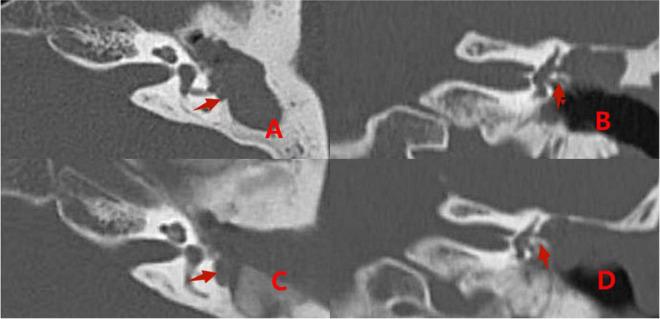

In group 1, from January 2008 to December 2014, 29 patients with middle ear cholesteatoma complicated by labyrinthine fistulas were treated with surgery involving covering the fistulas with simple fascia. In group 2, from January 2015 to October 2021, 36 patients with middle ear cholesteatoma complicated by labyrinthine fistulas were included. Cholesteatomas on the surface of type I labyrinthine fistulas were cleaned using the "under water technique" and capped with a "sandwich" composed of fascia, bone meal, and fascia. Cholesteatomas on the surface of type II and III fistulas were cleaned using the "under water technique," and the labyrinthine fistula was plugged with a "pie" composed of fascia, bone meal, and fascia, and then covered with bone wax.

Some patients with labyrinthine fistulas in group 1 exhibited symptoms of vertigo after surgery. In group 2 Patients with type II labyrinthine fistulas experienced short-term vertigo after semicircular canal occlusion, but no cases of vertigo were reported during long-term follow-up. "sandwich." In patients with type II labyrinthine fistulas, the semicircular canal occlusion influenced postoperative hearing improvement. However, postoperative patient hearing was still superior to preoperative hearing.

The surface of type I labyrinthine fistulas should be capped by a "sandwich" composed of fascia, bone meal, and fascia. Type II and III labyrinthine fistulas should be plugged with a "pie" composed of fascia, bone meal, and fascia, covered with bone wax.